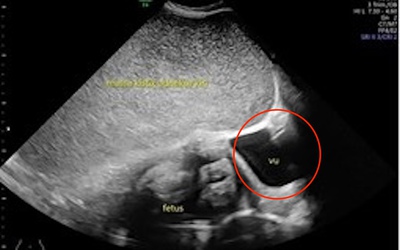

Thai phụ 26 tuổi kêu đau dạ dày, bác sĩ sốc nặng khi phát hiện "bí mật" đáng sợ

Các bác sĩ phát hiện một khối u nang lớn phát triển xung quanh thai nhi sau khi người mẹ báo cáo bị đau dạ dày.